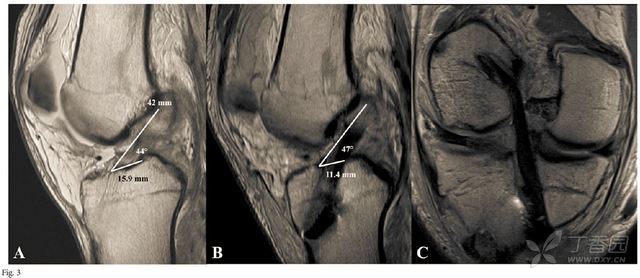

(d1) and posterior (d2) articular surface at blumensaats line

(a) the fibula points to the posterior half of the blumensaat

a 线);2分别通过 blumensaat 线的后角(图中 b 线)和股骨后髁轮